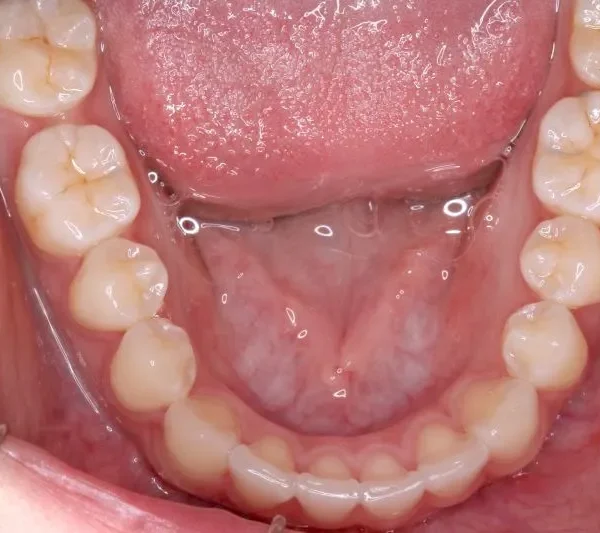

治療経過1

治療回数54回、9年3ヶ月の治療期間で矯正治療を終了しました。

噛み合わせのずれは、ぱっと見綺麗に見えますが、放っておくとのちのち噛みにくくなり、顎関節にまで影響を及ぼしかねません。

なので、見た目に関わらず噛みにくいとかんじたら、1度受診されることをオススメします。